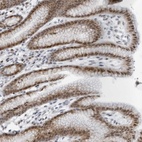

Immunohistochemical staining of human stomach shows moderate nuclear positivity in glandular cells.